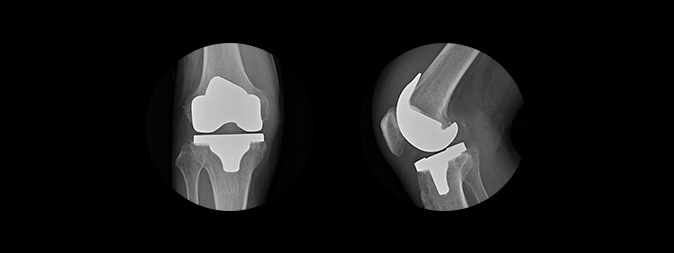

인공관절 전치환술

수술방법

무릎 관절 전체를

새로운 인공관절로 교체하는 수술

치료대상

무릎 관절이 전반적으로 손상된 경우